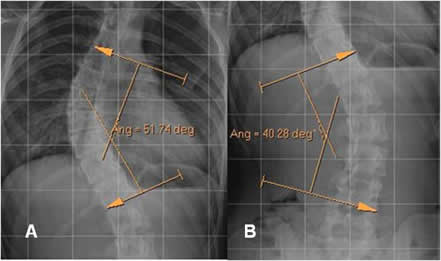

Fig 28. Angulo de Cobb.

Rx AP. Trazado entre las perpendiculares sobre el borde superior de la vértebra límite proximal y el borde inferior de la vértebra límite distal.

Fig 29. Angulo de Cobb.

A y B: Rx AP. Ejemplos de la medición del ángulo de Cobb, utilizando el software del visor.